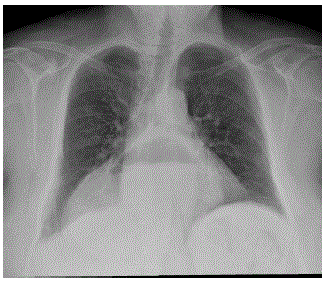

Homem de 27 anos de idade apresenta quadro de artropatia inflamatória de membros inferiores, associada às alterações de exame clínico mostradas a seguir.

Considerando a principal hipótese diagnóstica, qual é a manifestação ocular mais comum?